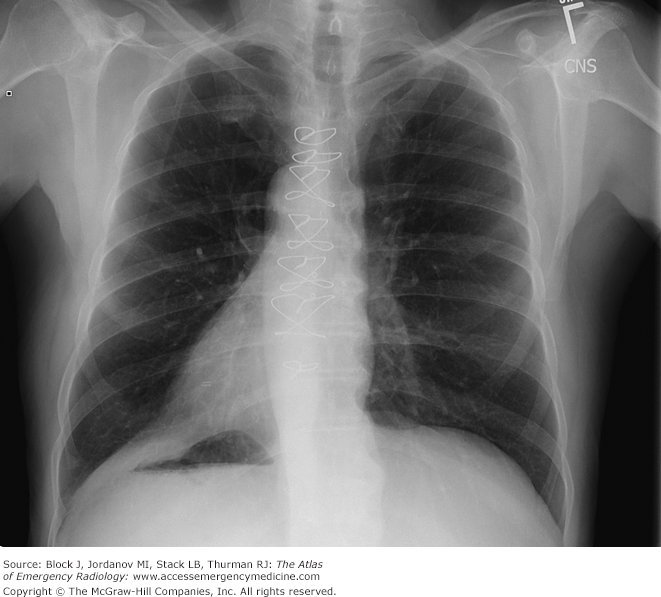

Cardiothoracic ratio

Cardiothoracic ratio: widest transverse diameter of the heart compared with the widest internal diameter of the rib cage (from inside of rib to inside of rib at the level of the diaphragm)

In most normal adults at full inspiration, the cardiothoracic ratio is less than 50%

Normal CT ratio should be less than or equal to 50%

Cardiothoracic ration